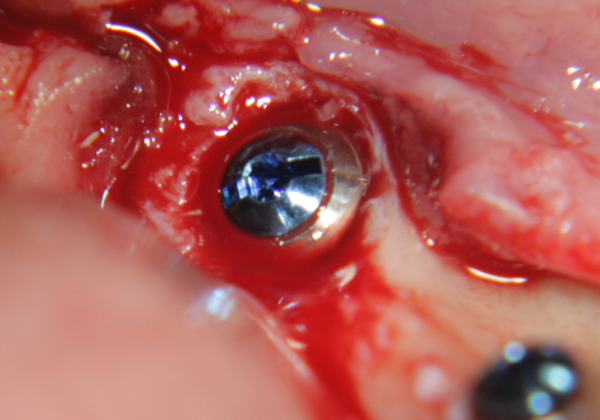

Имплантатът е поставен в костта. Вижда се покривният винт, който е оцветен в синьо. В периферията се вижда т.нар. bevel design на имплантатите - скосен дизайн, който улеснява работата на имплантолога и най-вече на вносителя на имплантатната система. Улеснението е голямо - скосеният дизайн позволява да се прилагат универсални надстройки за по-тесни и по-широки импланти. Освен това скосяването на имплантата предпазва от костна загуба - възпалителният инфилтрат от операцията мигрира над импланта и медиаторите на възпалените упражняват своето действие там. Някои от тези медиатори могат да причинят тъканна автолиза; очевидно не е възможно да разрушат титана. Повече информация за вътрекостните импланти... При гореописаната клинична ситуация е напълно възможно да се изчака много кратък оздравителен период и да се постави надстройка и корона, т.е. да се извърши имедиатно имплантиране + имедиатно натоварване. Така и постъпихме в случая. Спрямо научните схващания от 80-те и началото на 90-те години това е звучало като ерес и е било достатъчно основание извършителят да бъде разпънат на кръст, изгорен на клада или обесен, а понякога и двете заедно; в днешно време обаче има достатъчно натрупани клинични наблюдения и до голяма степен такъв тип лечение се превръща в стандартна процедура. Вход в нашия форум

На горната снимка се вижда къс имплант с широк диаметър, подходящ за имедиатно имплантиране. В областта на имплантатната шийка има разширение, което изпълва алвеолата и в много случаи не остава костен дефект - няма необходимост от костна пластика. Зъбният имплант на горната снимка е от серията Superline на производителя Dentium от Южна Корея. Тази имплантатна серия много прилича на серията IS1 на производителя Neobiotech, описана по-долу.